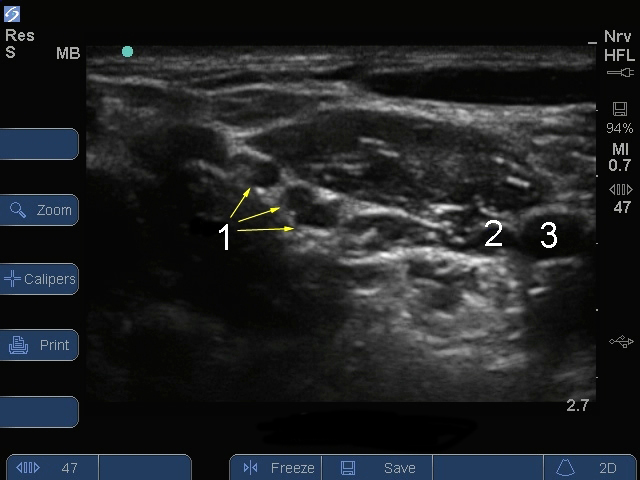

Serie S: Nivel interescalénico del plexo braquial - Imagen1

Nervio

Vena

Arteria